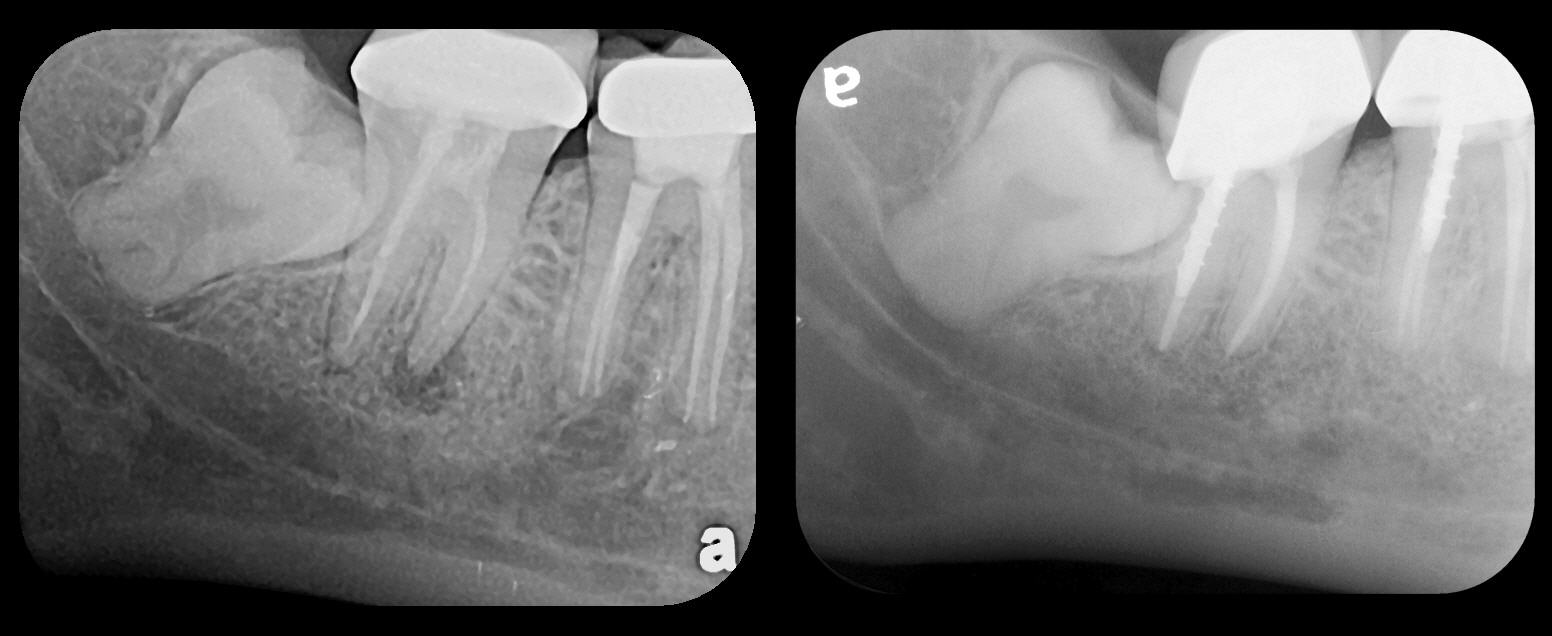

Fig 3. Two PSP PA radiographs of mandibular teeth showing: left, the initial view

of molar area and suspected pathology surrounding impacted tooth No. 32; center,

subsequently exposed PA radiograph, placed more distally, demonstrates extent

of large cyst as well as entire tooth and root No. 32. Proper alert as to presence

of suspected cyst and appropriate referral for 3D CBCT study and surgical

enucleation was given to the patient. Right: Same radiograph as on the left, but

with lighter superimposed outline of the area that would be visible using an HW

sensor rather than a PSP sensor. The small area of pathology is likely obscured

because it is visually overlaid by the root of tooth No. 31. Neglect of this significant

pathology may have resulted.

Figure 3